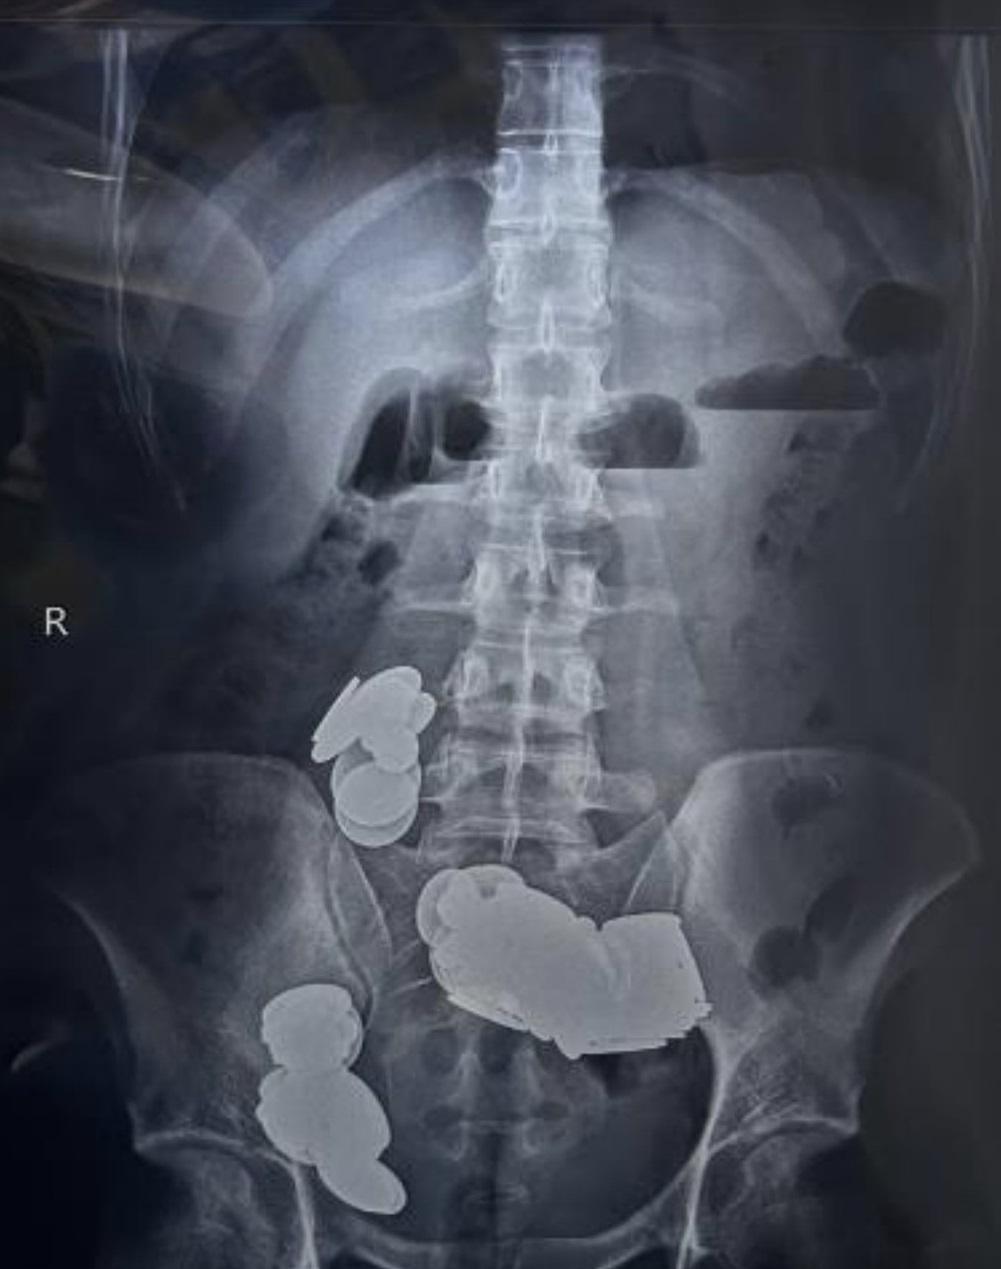

醫生在青年的胃部和小腸取出大量硬幣和磁鐵。(互聯網)

《印度時報》周二(27日)報道,醫生從這名男子的胃部和小腸合共取出39枚硬幣和37粒不同形狀的磁鐵。醫生表示,他相信硬幣含有鋅,有助健身,所以吞下這麼許多硬幣,吞磁鐵則是希望把硬幣吸在體內,不被排出。

男子經歷20多天劇烈腹痛、嘔吐、無法進食之後,終在家人陪同下到急症室求醫,經X光及電腦掃描檢查發現,他肚子裡塞滿硬幣,同時磁鐵已將小腸的不同環道吸在一起,造成腸塞。

男子的胃部和腸藏塞滿硬幣和磁鐵。(互聯網)